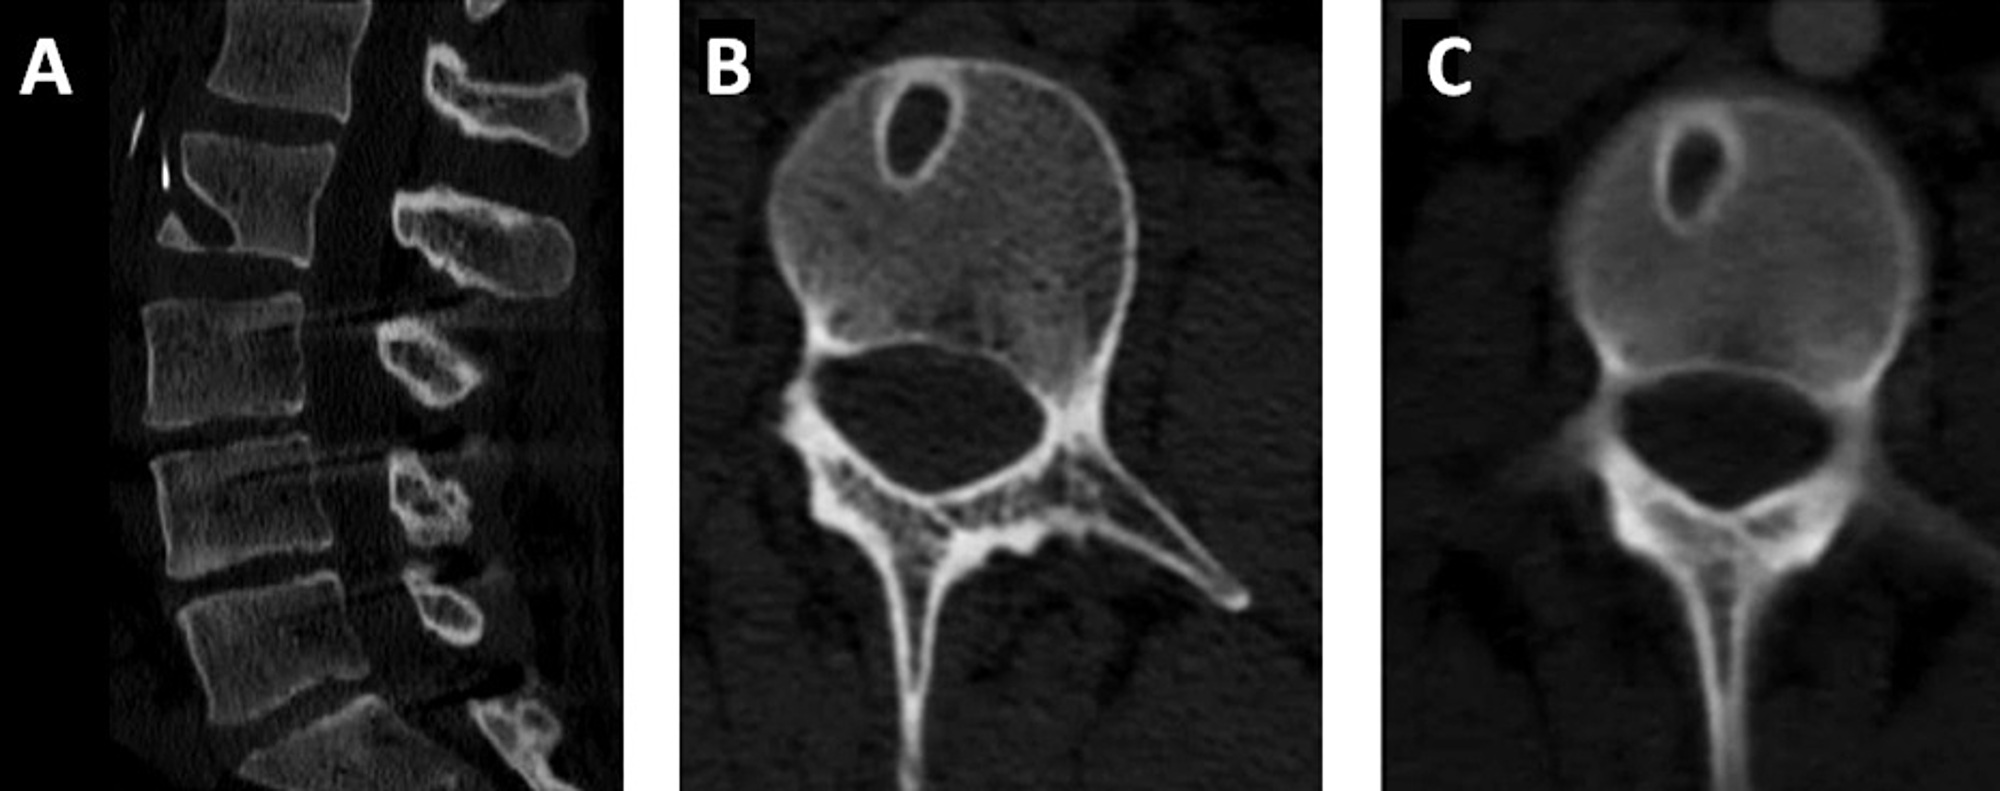

From www.semanticscholar.org

Chronic dura erosion and intradural lumbar disc herniation CT and MR Spinal Erosion Treatment This article describes the various treatments available to manage the symptoms. In this procedure, the damaged disk is removed and replaced by bone that connects to the. you can look after your spinal discs by maintaining good posture and a healthy weight, practising safe lifting and doing. mri will show enlargement of the spinal canal with arachnoid diverticulae,. Spinal Erosion Treatment.